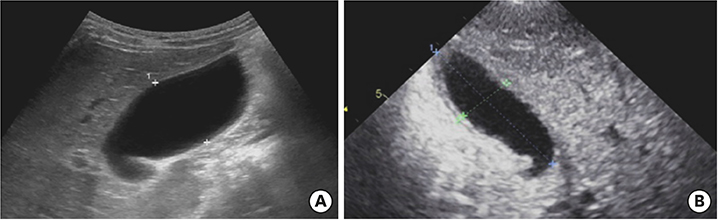

Laboratory findings showed neutrophilic leukocytosis (22,560 cells/mm3, with 81% neutrophils), elevated erythrocyte sedimentation rate (118 mm/hr), C-reactive protein (CRP) (19.8 mg/dL), brain natriuretic peptide (BNP) (1,022 pg/mL), and decreased sodium (131 mEq/L). Liver function tests were hyperbilirubinemia (total bilirubin, 3.4 mg/dL) as well as elevation of aspartate transaminase (AST) (155 U/L) and alanine transaminase (ALT) (418 U/L). His abdomen radiograph revealed modest shadowing of GB distension and no specific findings (Fig. 1A and B).

Abdominal radiograph supine view (A) and erect view (B) indicated modest shadowing of gallbladder distension.

Fig. 1 Abdominal radiograph supine view (A) and erect view (B) indicated modest shadowing of gallbladder distension.